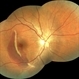

By Deepak Bhojwani, MS

- Uploaded on Feb 10, 2018.

- macula-on fresh superior retinal detachment

- Dr Deepak Bhojwani, Raghudeep Eye Hospital , Ahmedabad

- Fundus camera

- A 60 year old gentlemen came rushing to the retinal clinic with history of sudden onset of loss of inferior visual field since last 3 hours. Fundus photograph indeed corelates with his complaints documenting fresh superior macula-on rhegmatogenous retinal detachment.